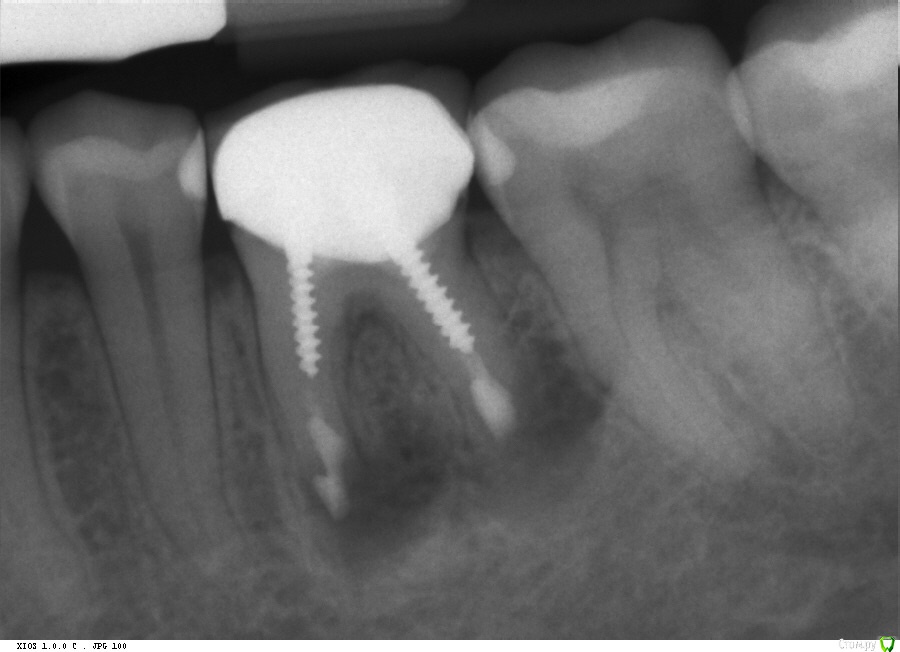

pin-up Опубликовано 28 августа, 2015 Поделиться Опубликовано 28 августа, 2015 Дорогие доктора!!У меня разболелся пятый зуб. Десна около него была красной и больно было надкусывать. А возле него у меня был плохой зуб, который я упорно спасала ( снимок был сделан сразу после резекции шестерки). Моя доктор сказала, что пятый зуб здоров, и скорей всего шестой зуб дает воспаление и из-за него страдает пятый. Короче говоря, удалили мне шестой зуб. Но пятый все также болит, при надкусывании и постукивании по нему. Симптомы могут проходить, но через пару дней опять начинает болеть. Прям не знаю что делать. Посоветуйте что-нибудь, пожалуйста. Ссылка на комментарий

sydnik Опубликовано 28 августа, 2015 Поделиться Опубликовано 28 августа, 2015 для начала новый снимок. Ссылка на комментарий

DR.P Опубликовано 28 августа, 2015 Поделиться Опубликовано 28 августа, 2015 Ждем новый снимок Ссылка на комментарий

pils Опубликовано 29 августа, 2015 Поделиться Опубликовано 29 августа, 2015 (изменено) Зачем? Все тоже самое, только отсутствует шестерка. Снимок относительно свежий Чтобы комментировать АКТУАЛЬНОЕ состояние Вашего зуба, нужны хоть какие-то АКТУАЛЬНЫЕ объективные данные. Объективным может быть фото хорошего качества и рентген. Изменено 29 августа, 2015 пользователем pils 1 Ссылка на комментарий